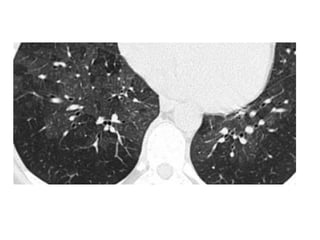

HRCT scan shows subpleural areas of ground-glass attenuation